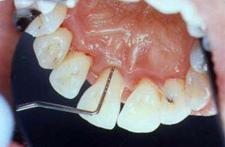

Sanatate parodontala

culoare roz coral

gingia este ferm atasata de dinte

lipsa sângerarii

aspect de "gravura punctata"